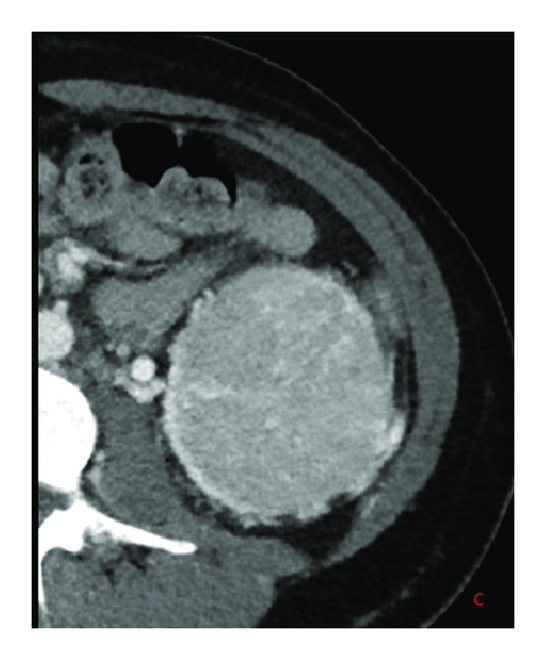

A 34-year-old female was seen in the emergency department for abdominal pain. Her workup included a CT abdomen where she was found to have bilateral renal masses: 2.4cm on the right and 7.6 cm on the left (Figure 1). Also noted were multiple small cysts in the lung bases. The rest of the workup was unremarkable and her abdominal pain resolved with conservative management alone. She was referred to urology where it was recommended that her left kidney tumor be resected and to defer the right pending pathology results. Notably, she had no prior medical history and no relevant surgical history and had otherwise been healthy and well. She has two siblings without lung, skin, or kidney symptoms and her parents are likewise healthy. She has a 15-year-old son who is healthy. There were no consistent skin findings on exam.

(c)

Pulmonary evaluation with a CT of chest identified basilar predominant multiple lung cysts with the largest cysts measuring approximately 1.6cm. Several <6mm partially solid nodules were noted as well. Spirometry, diffusion capacity, and plethysmography were all within normal limits. She did complain of mild dyspnea, but that this was intermittent and had a significant anxiety component.